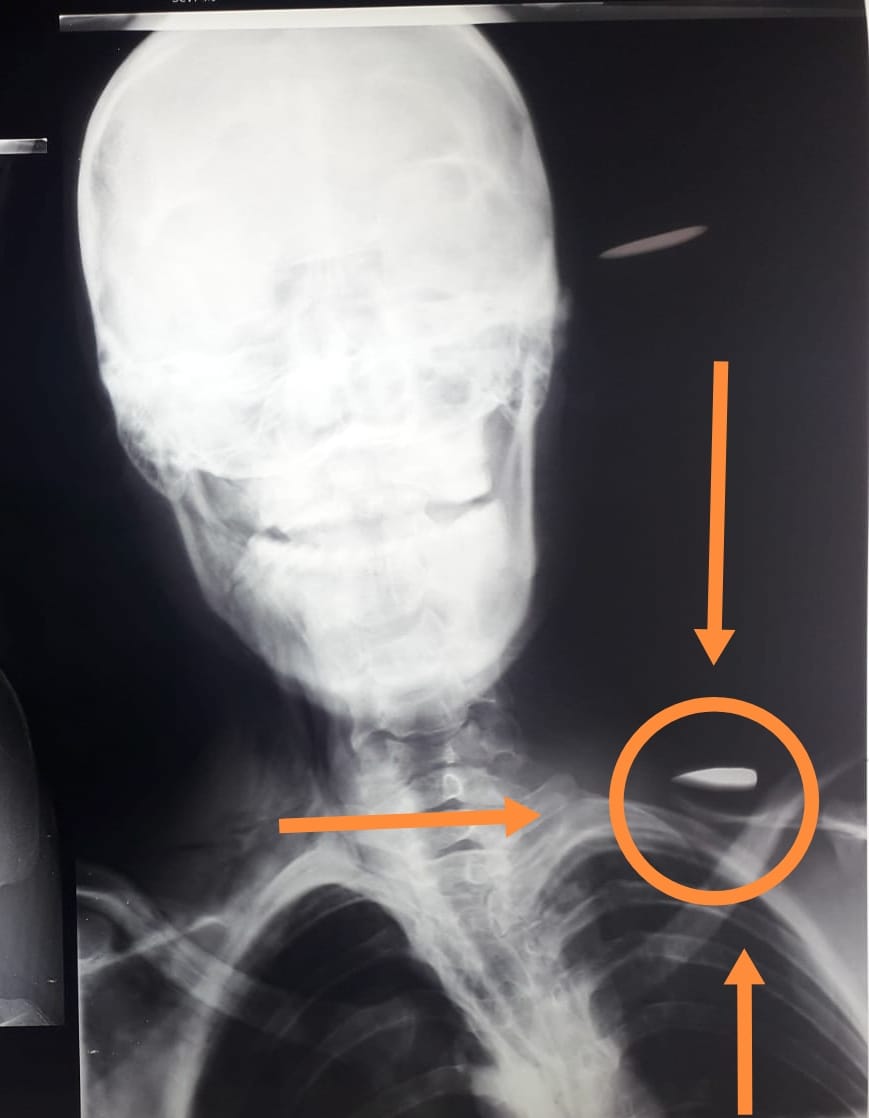

Margarita Moreno, madre de Ulises Salas Moreno, de 21 años, quien presenta una herida de bala en el cuello, que le afectó un pulmón, el cual ya fue sometido a una intervención quirúrgica en el Hospital de Especialidades, señaló que los militares fueron y les dijeron que iban a pagar “pero ya no regresaron, tampoco dinero no, no dejaron nada. No sé, la verdad, uno no tiene que echar mentiras”.

El joven estaba en su casa cuando los soldados empezaron a disparar, salió a la calle y un proyectil lo hirió en el cuello, afectando al pulmón y su estado es grave.